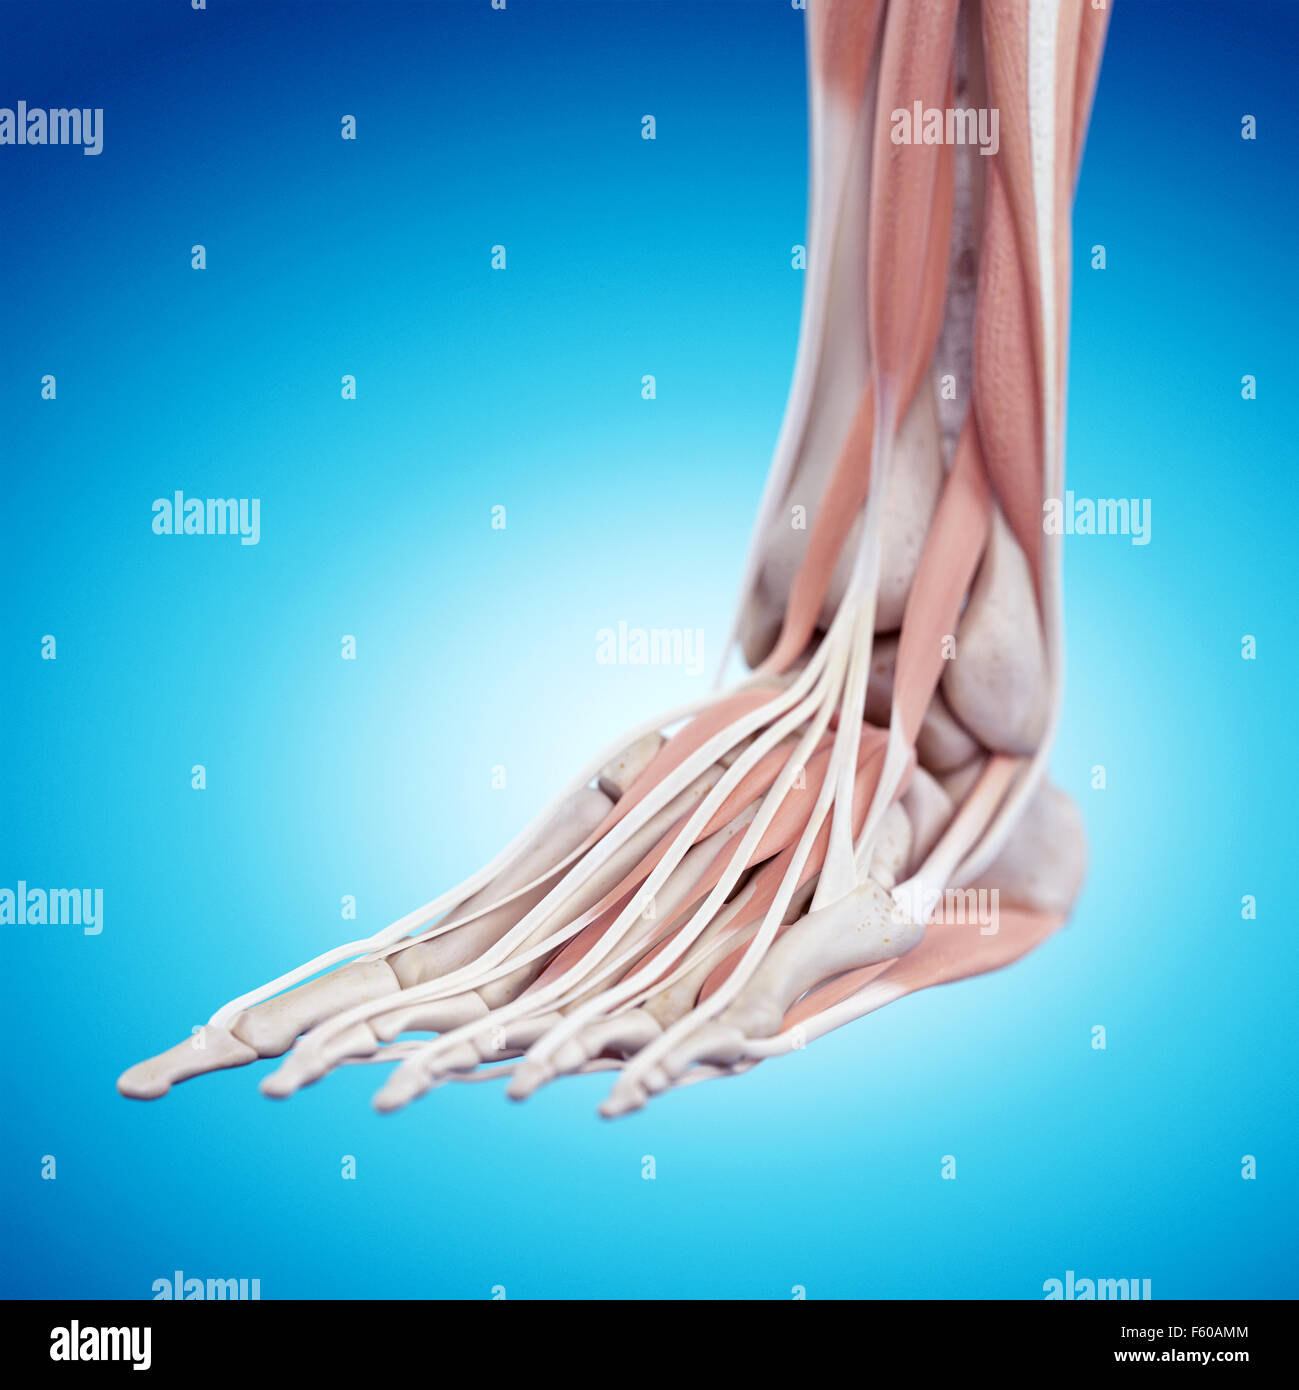

RF2HJXCXK–Anatomie du pied.OS et fascia Plantar.Illustration vectorielle réaliste. Vue de dessous et vue latérale